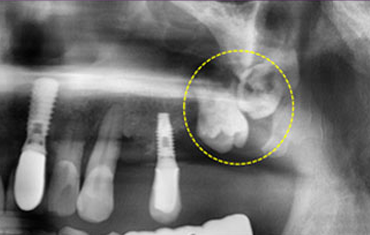

윗턱뼈에 사랑니가 매복된 경우

매복된 제2 대구치

매복된 사랑니

치료 전

치료 후윗턱뼈 공기주머니에 뼈이식